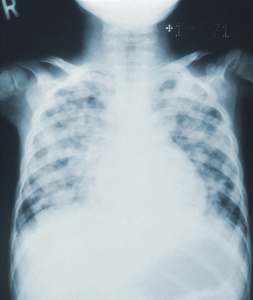

Three days after he’d been placed into isolation, my brother developed breathing problems. His doctor raced into our part of the room and led us into the hallway.

In a near-whisper, he said, “I’m glad you were already here. Your son is experiencing serious breathing issues so the Polio team wants him to go into an iron lung for a few days. It should minimize stress on his chest and that can help his recovery.” He explained, then added, “He’s a lucky boy! His Polio is a milder strain than what we’ve seen so far!”